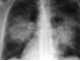

98.患者输液过程中突发胸闷,气急,咳痰,胸部正侧位片如图,最可能的诊断为()